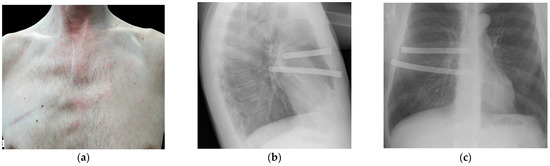

2. Materials and Methods

3. Results and Discussion